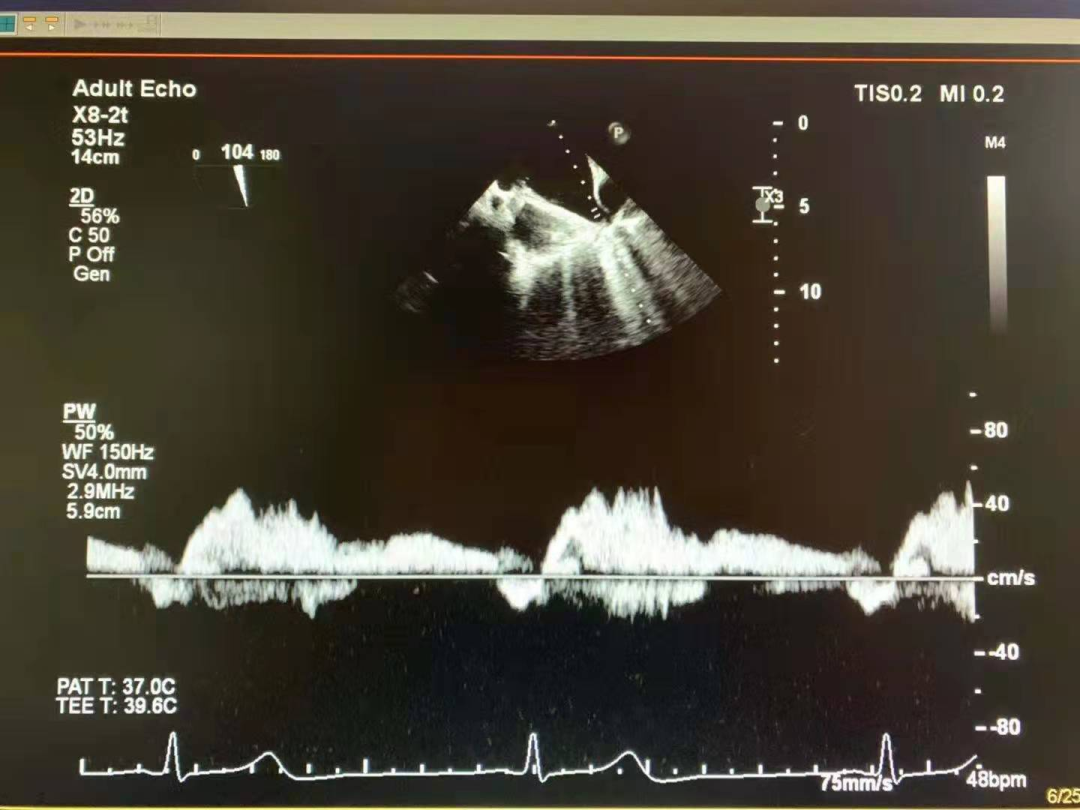

术前,罗建方、范瑞新教授团队进行了多次缜密术前讨论,最后决定为患者采用DragonFly™二尖瓣瓣膜夹。经充分的术前讨论后,心内科罗建方、范瑞新教授团队,在超声指导下,麻醉和体外循环团队保驾护航,瓣膜夹平稳释放,成功植入一枚DragonFly™瓣膜夹,随即进行DSA及心脏超声复查,观察到植入的瓣膜夹位置精确,患者二尖瓣反流从4+减少到1+以下,手术取得了圆满成功。